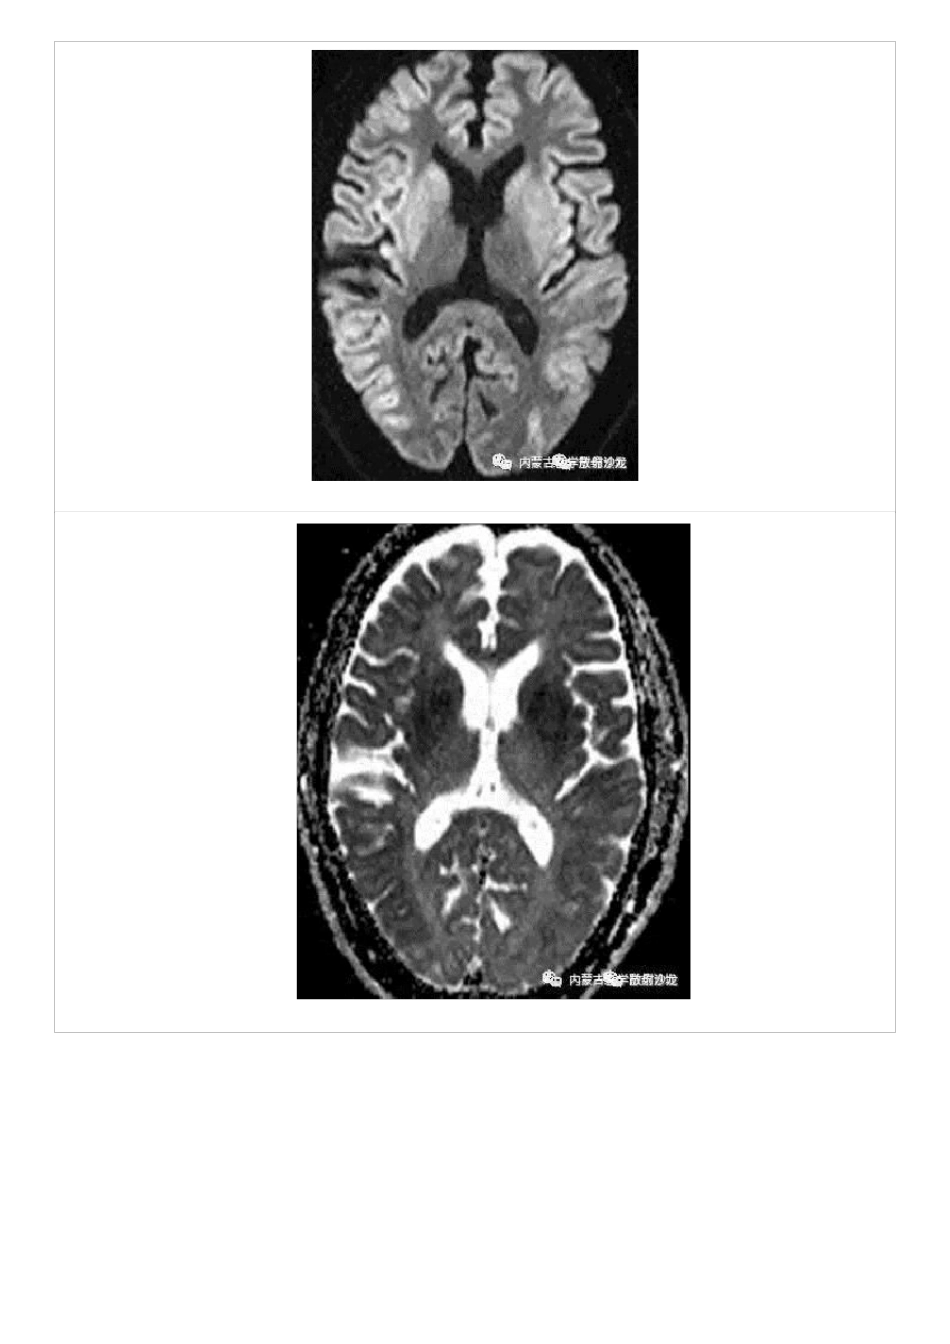

低血糖脑病的 MRI 表现及鉴别低血糖脑病可发生于任何年龄,多见于中老年人,有糖尿病史和降糖药物服用史,常发生在胰岛素使用过量的患者,血糖水平低于 2.8mmol/L(50 ml/dl),老年人对降糖药物,特别是磺脲类药物耐受性差。也可见于酗酒、节食减肥、饥饿、胰岛细胞瘤患者。脑组织对低血糖的耐受性是不一致的,越是进化发育程度高的组织,对缺糖的敏感性高,耐受性越差;因此,低血糖发生时首先是大脑皮层出现抑制,其次是皮层下中枢包括基底节区、下丘脑、植物神经中枢相继受影响,接下来受影响的是间脑、中脑、脑干网状结构、延脑。补充葡萄糖后按上述顺序逆转恢复。脑实质受损主要累及皮质及深部核团,受损程度取决于低血糖严重程度及持续时间。影像表现主要有下面三种情况(a) 灰质受累为主:累及皮质、纹状体及海马等;(b) 白质受累为主:累及侧脑室周围白质、内囊及胼胝体压部;(c) 灰白质均受累。小脑和脑干是对低血糖神经损害具有较高耐受性的区域。低血糖脑病预后取决于低血糖持续时间、程度及机体状况。(低血糖损害中枢神经系统通常的顺序)新生儿脑代谢旺盛,低血糖脑病在婴儿中较常见,主要造成顶枕叶的不对称性损害,急性期 MRI 表现为顶枕叶皮层、皮层下斑片状长 T1WI、长 T2WI 信号,DWI呈高信号。成年人低血糖脑病常常累及大脑皮质、胼胝体、基底节区、海马等区域,对称或不对称,病灶呈稍长T1 稍长 T2 信号,FLAIR 高信号,DWI 高信号,ADC 低信号,MRA 未见相应供血区血管病变。纠正血糖后部分病灶可逆。仅累及胼胝体者预后较好。脑干和小脑对低血糖脑损伤具有相对较高的耐受性。(DWI 对病灶显示很有意义)(M/50 ,既往有糖尿病和高血压病史,目前处于昏迷状态,DWI 及相对应 ADC 图片提示双侧皮质、海马回、基底节区扩散受限,且呈对称性)鉴别诊断:包括克-亚氏病(CJD)、线粒体脑肌病、皮层脑梗死、病毒性脑炎、可逆性后部脑病综合征、肾上腺危象、渗透性脱髓鞘综合征、溶血性贫血、氰化物中毒、严重脑外伤等,应结合临床病史予以鉴别。克-亚氏病:CJD 包括散发型 CJD(sCJD)、遗传型(gCJD)、医源型 CJD(iCJD)及新变异型 CJD(vCJD)。MRI 最显著的特征是大脑皮层、双侧尾状核、壳核、丘脑,在 FLAIR 序列、T2WI 呈对称稍高信号,DWI 高信号,丘脑枕部见“曲棍球征”,MRI 动态观察常能在短期内显示脑实质的进行性萎缩。线粒体脑肌病:以皮质受累为主,并呈向皮层下白质蔓...